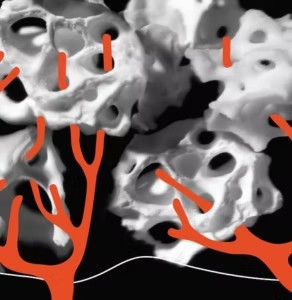

Po 2 tygodniach

W ciągu dwóch tygodni naczynia krwionośne przenikają przez pory materiału przeszczepowego, osadzając się i rozrastając w jego wnętrzu. To oznacza początkowy etap formowania się kości.